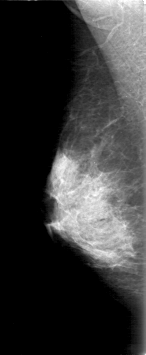

D_4168_1.RIGHT_MLO

ics_version 1.0

filename D-4168-1

DATE_OF_STUDY 9 11 1998

PATIENT_AGE 48

FILM_TYPE REGULAR

DENSITY 3

DATE_DIGITIZED 2 6 1999

DIGITIZER HOWTEK 43.5

RIGHT_CC LINES 4696 PIXELS_PER_LINE 2116 BITS_PER_PIXEL 12 RESOLUTION 43.5 NON_OVERLAY

RIGHT_MLO LINES 5311 PIXELS_PER_LINE 2176 BITS_PER_PIXEL 12 RESOLUTION 43.5 NON_OVERLAY